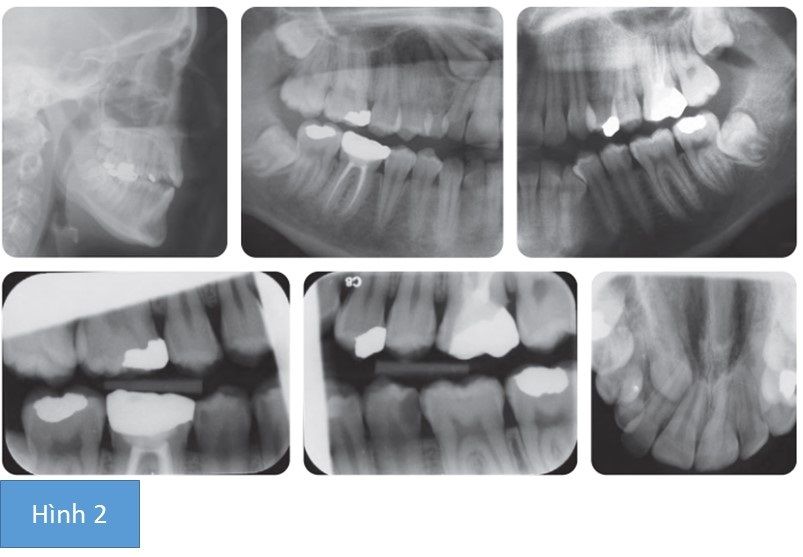

Bệnh nhân nữ 22 tuổi có tương quan răng cửa hạng III trên nền xương hạng I với chiều cao tầng mặt dưới phía trước tăng. Môi khép kín và hình ảnh mặt nghiêng tốt. Tất cả các răng vĩnh viễn đã xuất hiện trong miệng, ngoài trừ R13 và răng hàm lớn thứ 3. Vẫn còn răng hàm lớn thứ 3. Bộ răng đã được phục hồi tốt với R46 và R26 có phục hồi lớn bằng vàng.

Chen chúc nhẹ ở hàm dưới với R33 chen chúc và nghiêng xa. Ở cung hàm trên chen chúc nặng với R13 chưa mọc và mọc ngầm.

Đối với khớp cắn, tương quan răng cửa hạng III cùng với cắn hở phía trước 1mm. Tương quan răng hàm lớn là hạng III ¼ đơn vị 2 bên và đường giữa hàm dưới lệch trái 1 mm.

Với cung hàm dưới, khoảng tối ưu được cung cấp bằng cách nhổ răng hàm nhỏ thứ nhất hàm dưới, cung cấp khoảng trống để làm đều nhóm răng trước hàm dưới, kéo lùi chúng và giúp có được tương quan răng cửa hạng I. Tuy nhiên, R35 có phục hồi amalgam lớn, ảnh hưởng tủy nên có tiên lượng tuổi thọ kém. Thêm vào đó, R46 đã điều trị tủy và có thân răng trám vàng hoàn toàn. Do đó, nên nhổ các răng này ở cung hàm dưới mặc dù chúng không cung cấp khoảng trống tối ưu và thời gian điều trị có thể kéo dài hơn để đóng khoảng ở cung răng hàm dưới bên phải. R44 bị sâu ở phía xa được hàn bằng composite.

Ở cung hàm trên, để làm đều R13 thì cần phải nhổ R53, phẫu thuật bộc lộ R13 và kéo chỉnh nha. Cũng cần thêm khoảng trống vì thân R53 bé hơn R13. Cung răng trên chen chúc và để kéo R13 thì cần có neo chặn. Có một vài yếu tối bất lợi khi làm đều R13, như là vị trí bất lợi của R13 (cao và lệch về phía đường giữa) và tuổi của bệnh nhân. Hơn nữa, việc nhổ R14 khỏe mạnh để tạo đủ khoảng cho làm đều R13 là một phương án tiềm ẩn rủi ro nếu không thể kéo R13 xuống được. Nỗ lực làm răng nanh mọc lên cũng làm tăng đáng kể thời gian điều trị. Vì thế trong trường hợp này, quyết định nhổ R13 và R53. Với việc mất 2 răng vĩnh viễn ở cung hàm dưới và 1 răng ở cung hàm trên bên phải thì càn thiết phải nhổ răng ở cung hàm trên bên trái. Trong trường hợp này có 2 lựa chọn; hoặc là R24 hoặc là R26. R26 có phục hình lớn hơn nên quyết định nhổ R26. Sau khi nhổ những răng này, khí cụ cố định đã được gắn vào.